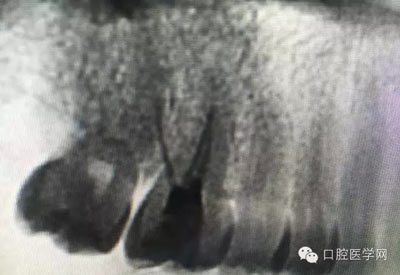

這是一例外院樹脂修復后十個月出現(xiàn)牙髓炎癥狀的患者。遇到這樣子的患者大家會怎么做,證明選擇,還有就是可做可不做治療的如何去平衡。